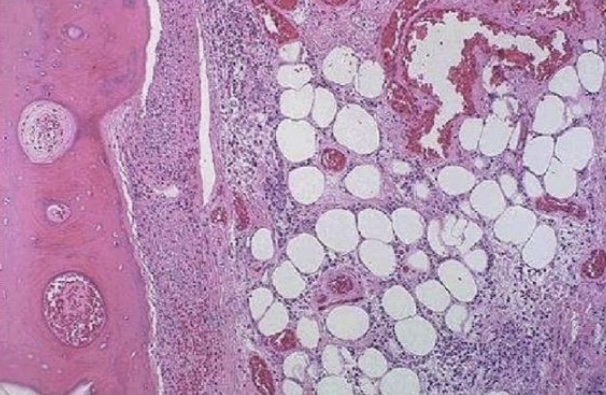

Depot fat

Fatty infiltration

Fatty degeneration